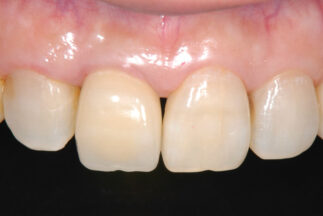

- Before